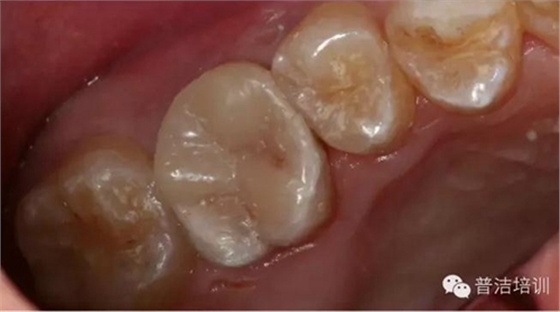

部分病例:

改變了什么?